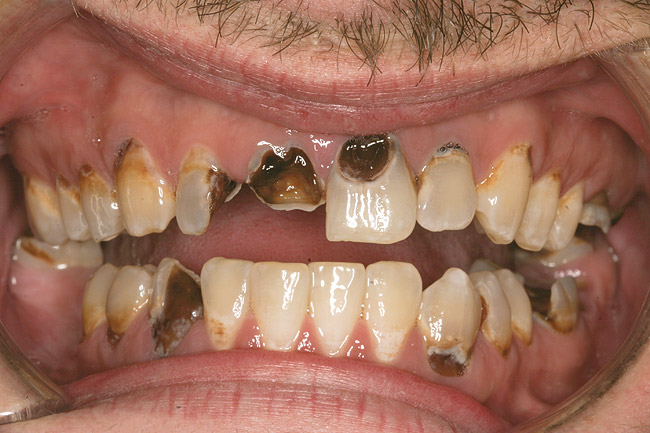

Figure 4  PRESENTATION CONDITION By the time Joe presented for treatment after serving time in prison and going to rehab, his teeth were completely destroyed by rampant decay. Although some teeth could have been saved, the patient chose to have all of the remaining teeth extracted in order to receive a set of full dentures.

Figure 4

Joe soon learned how to manufacture the drug. His need for meth soon consumed his every thought. He basically lived to do more meth. He admitted that he had made some poor choices. Unfortunately once the addiction kicked in, he no longer had a choice, he had to use. This was his end result (Figure 4 through Figure 6). From these photographs, one might think that he had used the drugs his entire life; however, this progression happened over the course of only about 1 year of smoking the drug. Because of the caustic chemicals (muriatic acid, hydrochloric acid, lithium, etc) his teeth started to blacken, then break.

As a new patient, Joe was instantly likable. He had a great sense of humor. He regretted how his life had turned out. When he finally presented to this author’s practice he was 24 years old. He wanted to remove the evidence of his addiction that were visible to anyone that came in contact with him. His teeth were totally destroyed by his drug use. There was no hope of saving any of them. There were horrible infections in his jaw bones that were spreading through his system. His only option was to remove all of his teeth and have dentures made. Impressions were taken with alginate. A bite was established in maximum intercuspation. We decided that his preoperative incisal edge positions of teeth Nos. 9 and 10 were adequate to recreate the incisal edge position in full dentures.